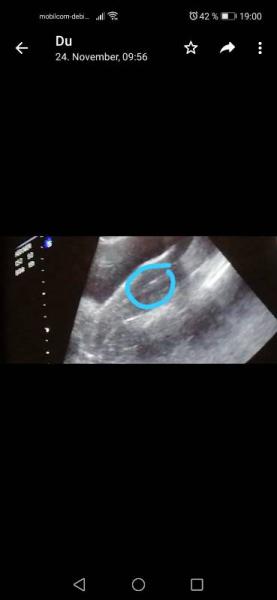

Da sind se

Bild zu

Ja das sind die beiden Aaber Klar sieht man noch kein Embryo aber das sind meine beiden eiers und ich fands nett, weil ich auch nachgefragt hab. Und ich Habs eingerahmt